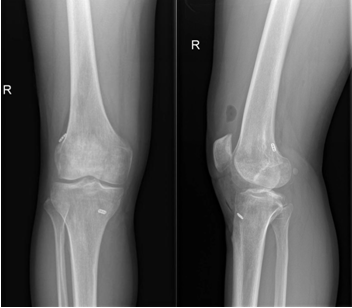

近日,一名31岁男性因打篮球扭伤致“右膝关节疼痛伴行走不稳半年”入院,术前诊断:前交叉韧带部分断裂。考虑患者年轻且有较高的运动恢复需求,在骨科病院刘时璋主任医师的指导下,由冯敏副主任医师主刀完成黑料网首例关节镜辅助下前交叉韧带损伤“保残+全内”重建术。患者第二日即下地活动,第三天顺利出院。

ACL的保残重建具有有效促进ACL移植物血管再生,促进损伤ACL本体感觉的恢复,以及防止ACL术后隧道扩大等多种技术优势。而ACL的全内重建技术是国际上新近发展出现的另一项新技术,相比传统方法,它仅需获取自身单根肌腱,而且所需长度远小于传统重建方法。另外,此技术保留了更多的骨皮质及骨膜,术后疼痛更少,腱骨愈合更佳,同时有效降低了术后感染风险,避免了传统方式界面螺钉对肌腱的切割作用。